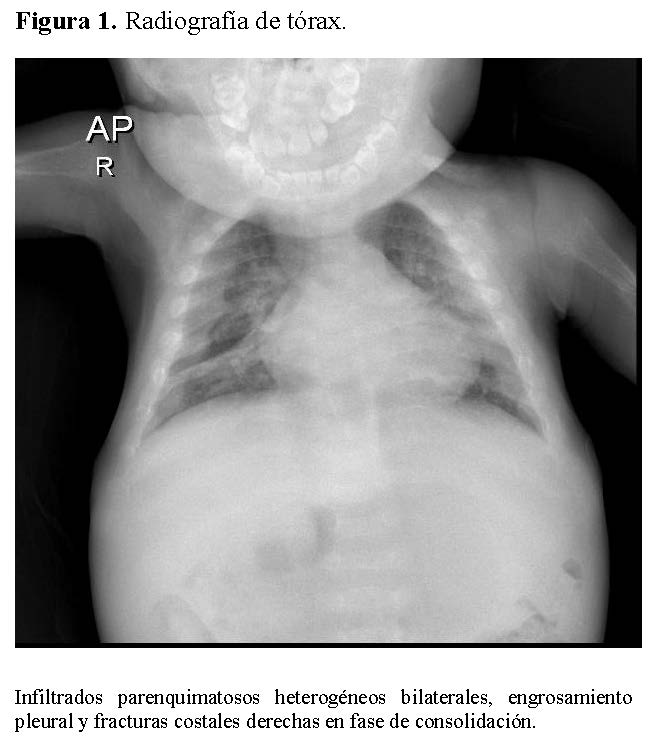

Chest radiography showed bilateral heterogeneous parenchymal infiltrates, pleural thickening, and right-sided rib fractures in the consolidation phase (Figure 1). Radiographs of long bones revealed severe osteopenia, periosteal reaction, and multiple pathological fractures, including the right and left humerus, right ulna, and right femur (Figures 2 and 3).

Figure 1.